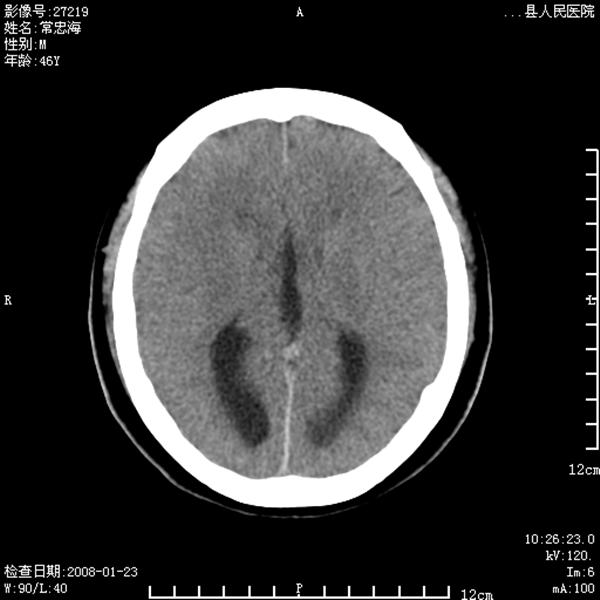

以下是引用江边学者在2008-4-19 22:26:00的发言:[br]1.胼胝体发育不良。[br]2.右侧眼球痨。[br]3.右侧颜面部软组织挫伤。